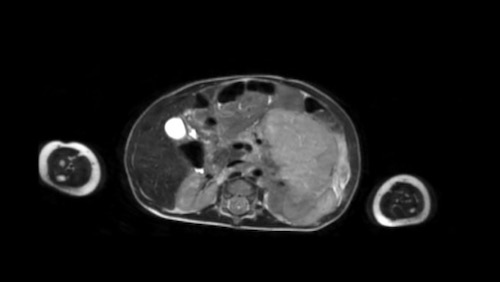

MRI shows a solid hepatic mass with multiple small cysts.

Sau khi tiêm thuốc cản quang, khối u được thấy giới hạn ở phân thùy sau và trước phải, được phân định bởi tĩnh mạch gan giữa (mũi tên).

The mass has moderate diffusion restriction.

Biopsy was compatible with an epithelial hepatoblastoma.